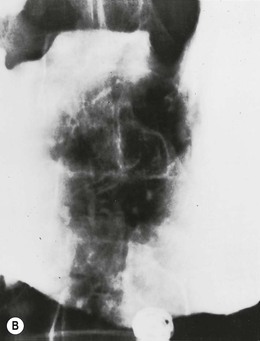

atrophic gastritis

Radiographic findings of atrophic gastritis include loss of rugal folds and a tubular, featureless narrowed stomach

Atrophic gastritis is a combination of atrophy of the gastric glands with histological inflammatory changes. Atrophic gastritis is found in more than 90% of patients with pernicious anaemia and is characterised by loss of parietal and chief cells, leading to achlorhydria, and atrophy of the mucosa and mucosal glands.35 Atrophic gastritis causes a decrease in the production of intrinsic factor, which in turn causes malabsorption of vitamin B12.